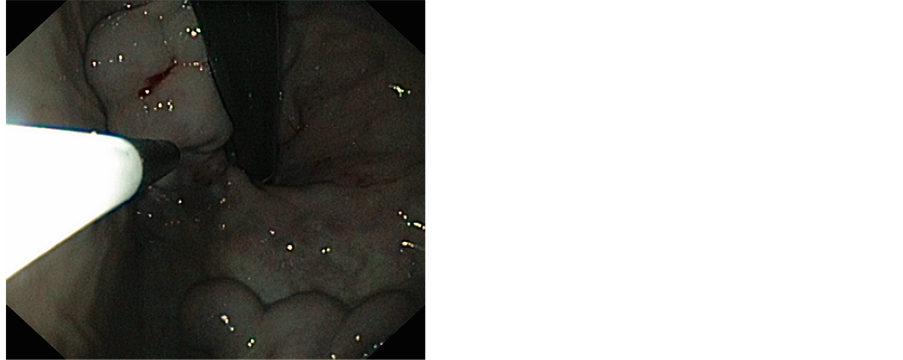

An endoscopy was performed 24 hours after the bleeding period and had objectified stage I of esophageal varices with some red signs associated with two large varices with red signs in cardia, the patient had received an injection of a chemical glue 1cc at the gastric varices without maternal neither fetal incident. An abdominopelvic ultrasound was performed and showed signs of portal hypertension and signs of chronic liver disease with progressive singleton pregnancy. The evolution was marked by a smooth pregnancy and delivery at term vaginally of a newborn male, birth weight 3000 g, APGAR 10/10 with good psychomotor development. Nine months later, the patient presented bleeding. An upper endoscopy showed a varicose vein in the cardia, which was treated by histoacryl of injection (Figures 1 and 2).

Figure 2. Injection of histoacryl.